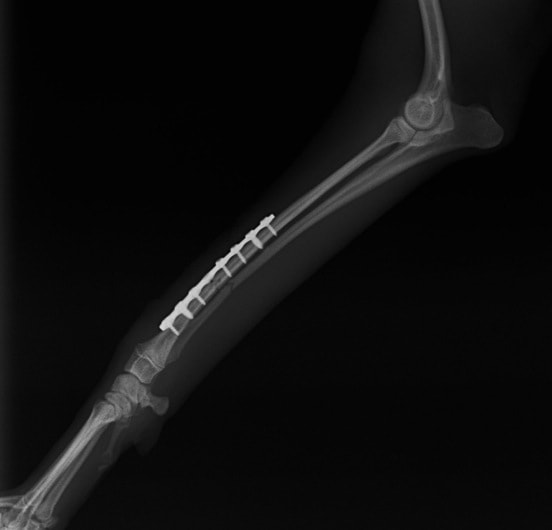

トイプードル 右遠位橈尺骨短斜骨折のALPSによる内固定